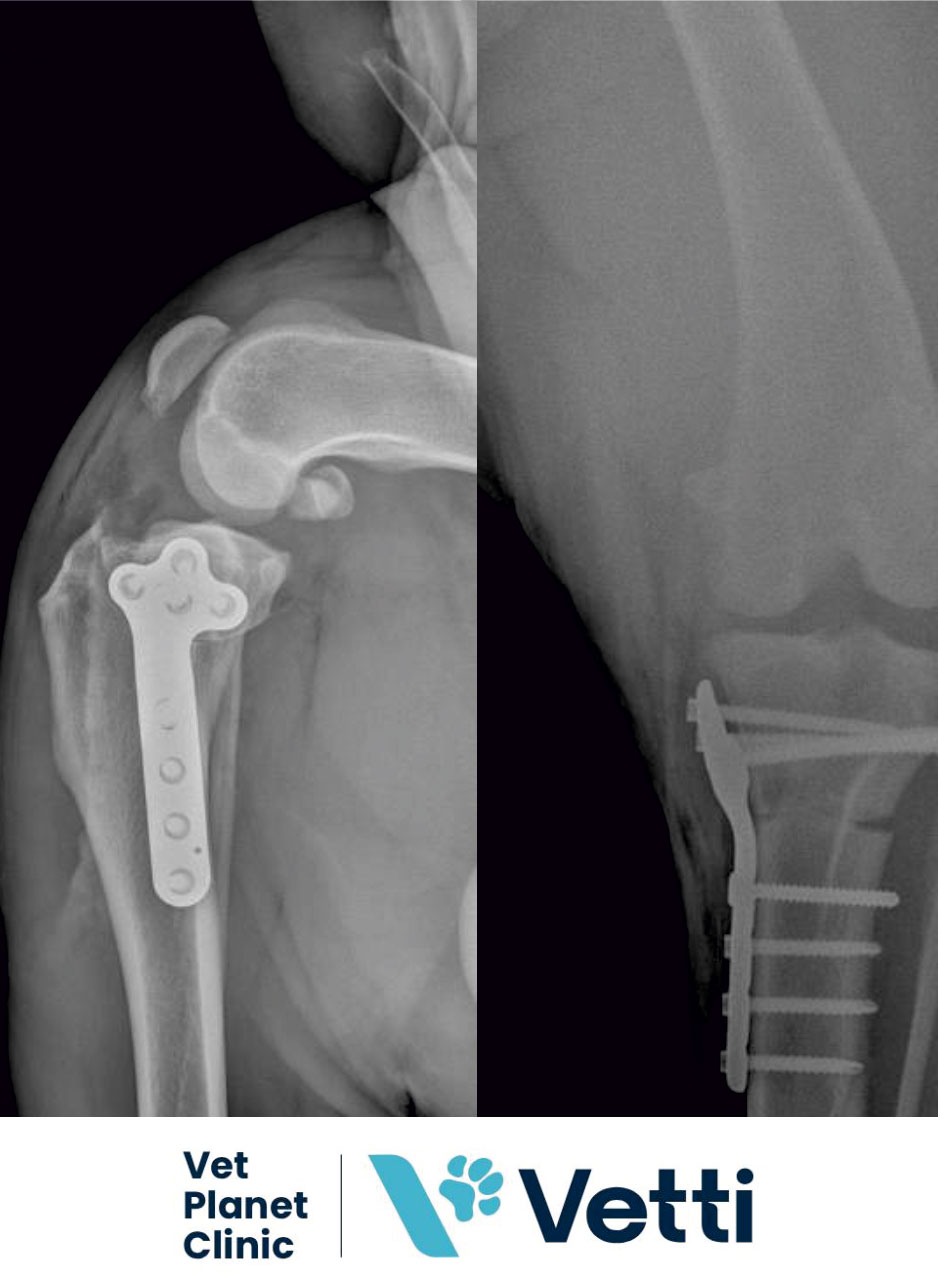

Pored laboratorije, Vet Planet je opremljen najsavremenijom dijagnostičkom opremom, uključujući ultrazvuk, digitalni rendgen i CT uređaj najnovije generacije. Moderna oprema nam svakodnevno omogućava visok nivo stručnosti, sigurnosti i kvaliteta u pružanju veterinarskih usluga.